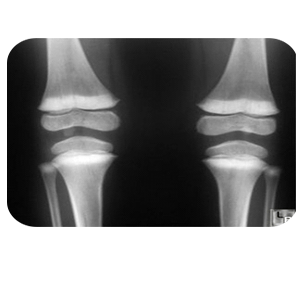

Units of the Department of Forensic Medicine and Clinical Toxicology Head of the Department's Message Services Units Academic Staff Course Description The department has the following devices and samples: